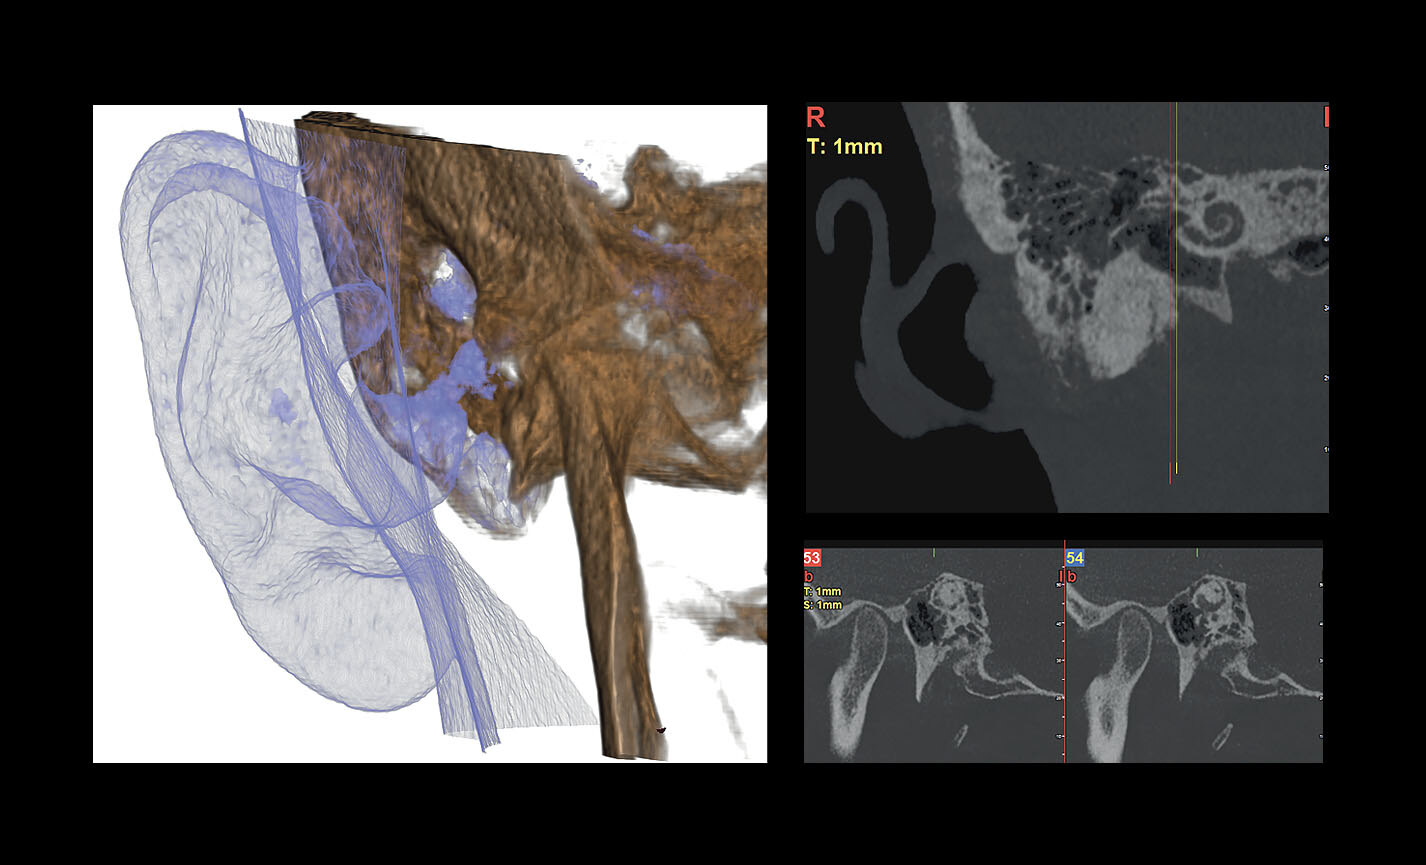

EXAMENS OTO-RHINO-LARYNGOLOGIQUES

Oreille : 7 x 6 cm (XF)

Articulation Temporo-Mandibulaire : 7 x 6 cm (XF) bouche ouverte/bouche fermée

Analyses volumétriques

La fonction du logiciel de calcul du volume de soulèvement du sinus maxillaire permet de déterminer l’intervention à l’avance et d’opérer en toute sécurité. Il est en outre possible de tracer des lignes directement sur le modèle virtuel du patient en évaluant les rapports morphologiques sur le rendu 3D.

Évaluation des implants zygomatiques

Les volumes avec FOV 13 x 8 cm, ou 13 x 10 cm, représentent l’outil idéal pour la planification des implants zygomatiques. En effet, le diamètre de 13 cm est le seul qui permet d’inclure tout le zygoma dans le balayage, sans coupes.